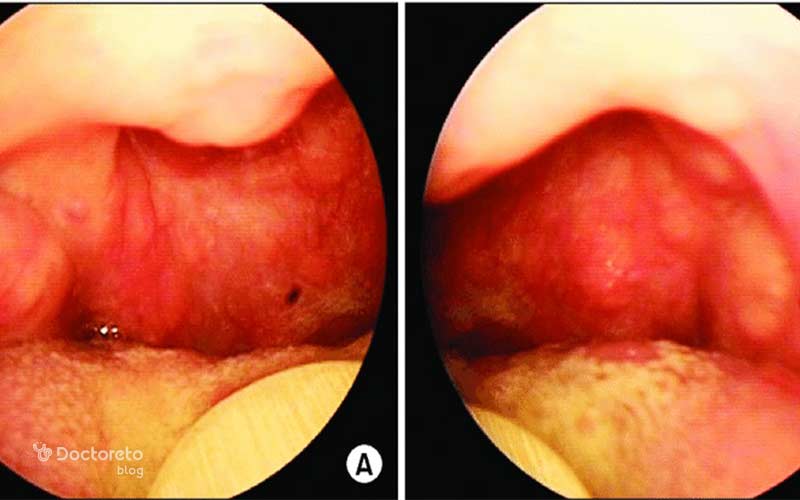

عکس لوزه بزرگ شده

لوزههای بزرگشده به صورت تودههای متورم در پشت گلو دیده میشوند. چنین لوزههایی ممکن است فضای راه هوایی را تنگ کنند. این وضعیت میتواند تنفس یا بلع را دشوار کند و در برخی افراد باعث گلودرد مداوم شود. در کودکان، بزرگ شدن لوزهها گاهی با خروپف شبانه یا اختلال در خواب همراه است. در صورت تداوم علائم یا ایجاد مشکل در تنفس، بررسی پزشکی برای تعیین علت و انتخاب روش درمان مناسب ضروری است.